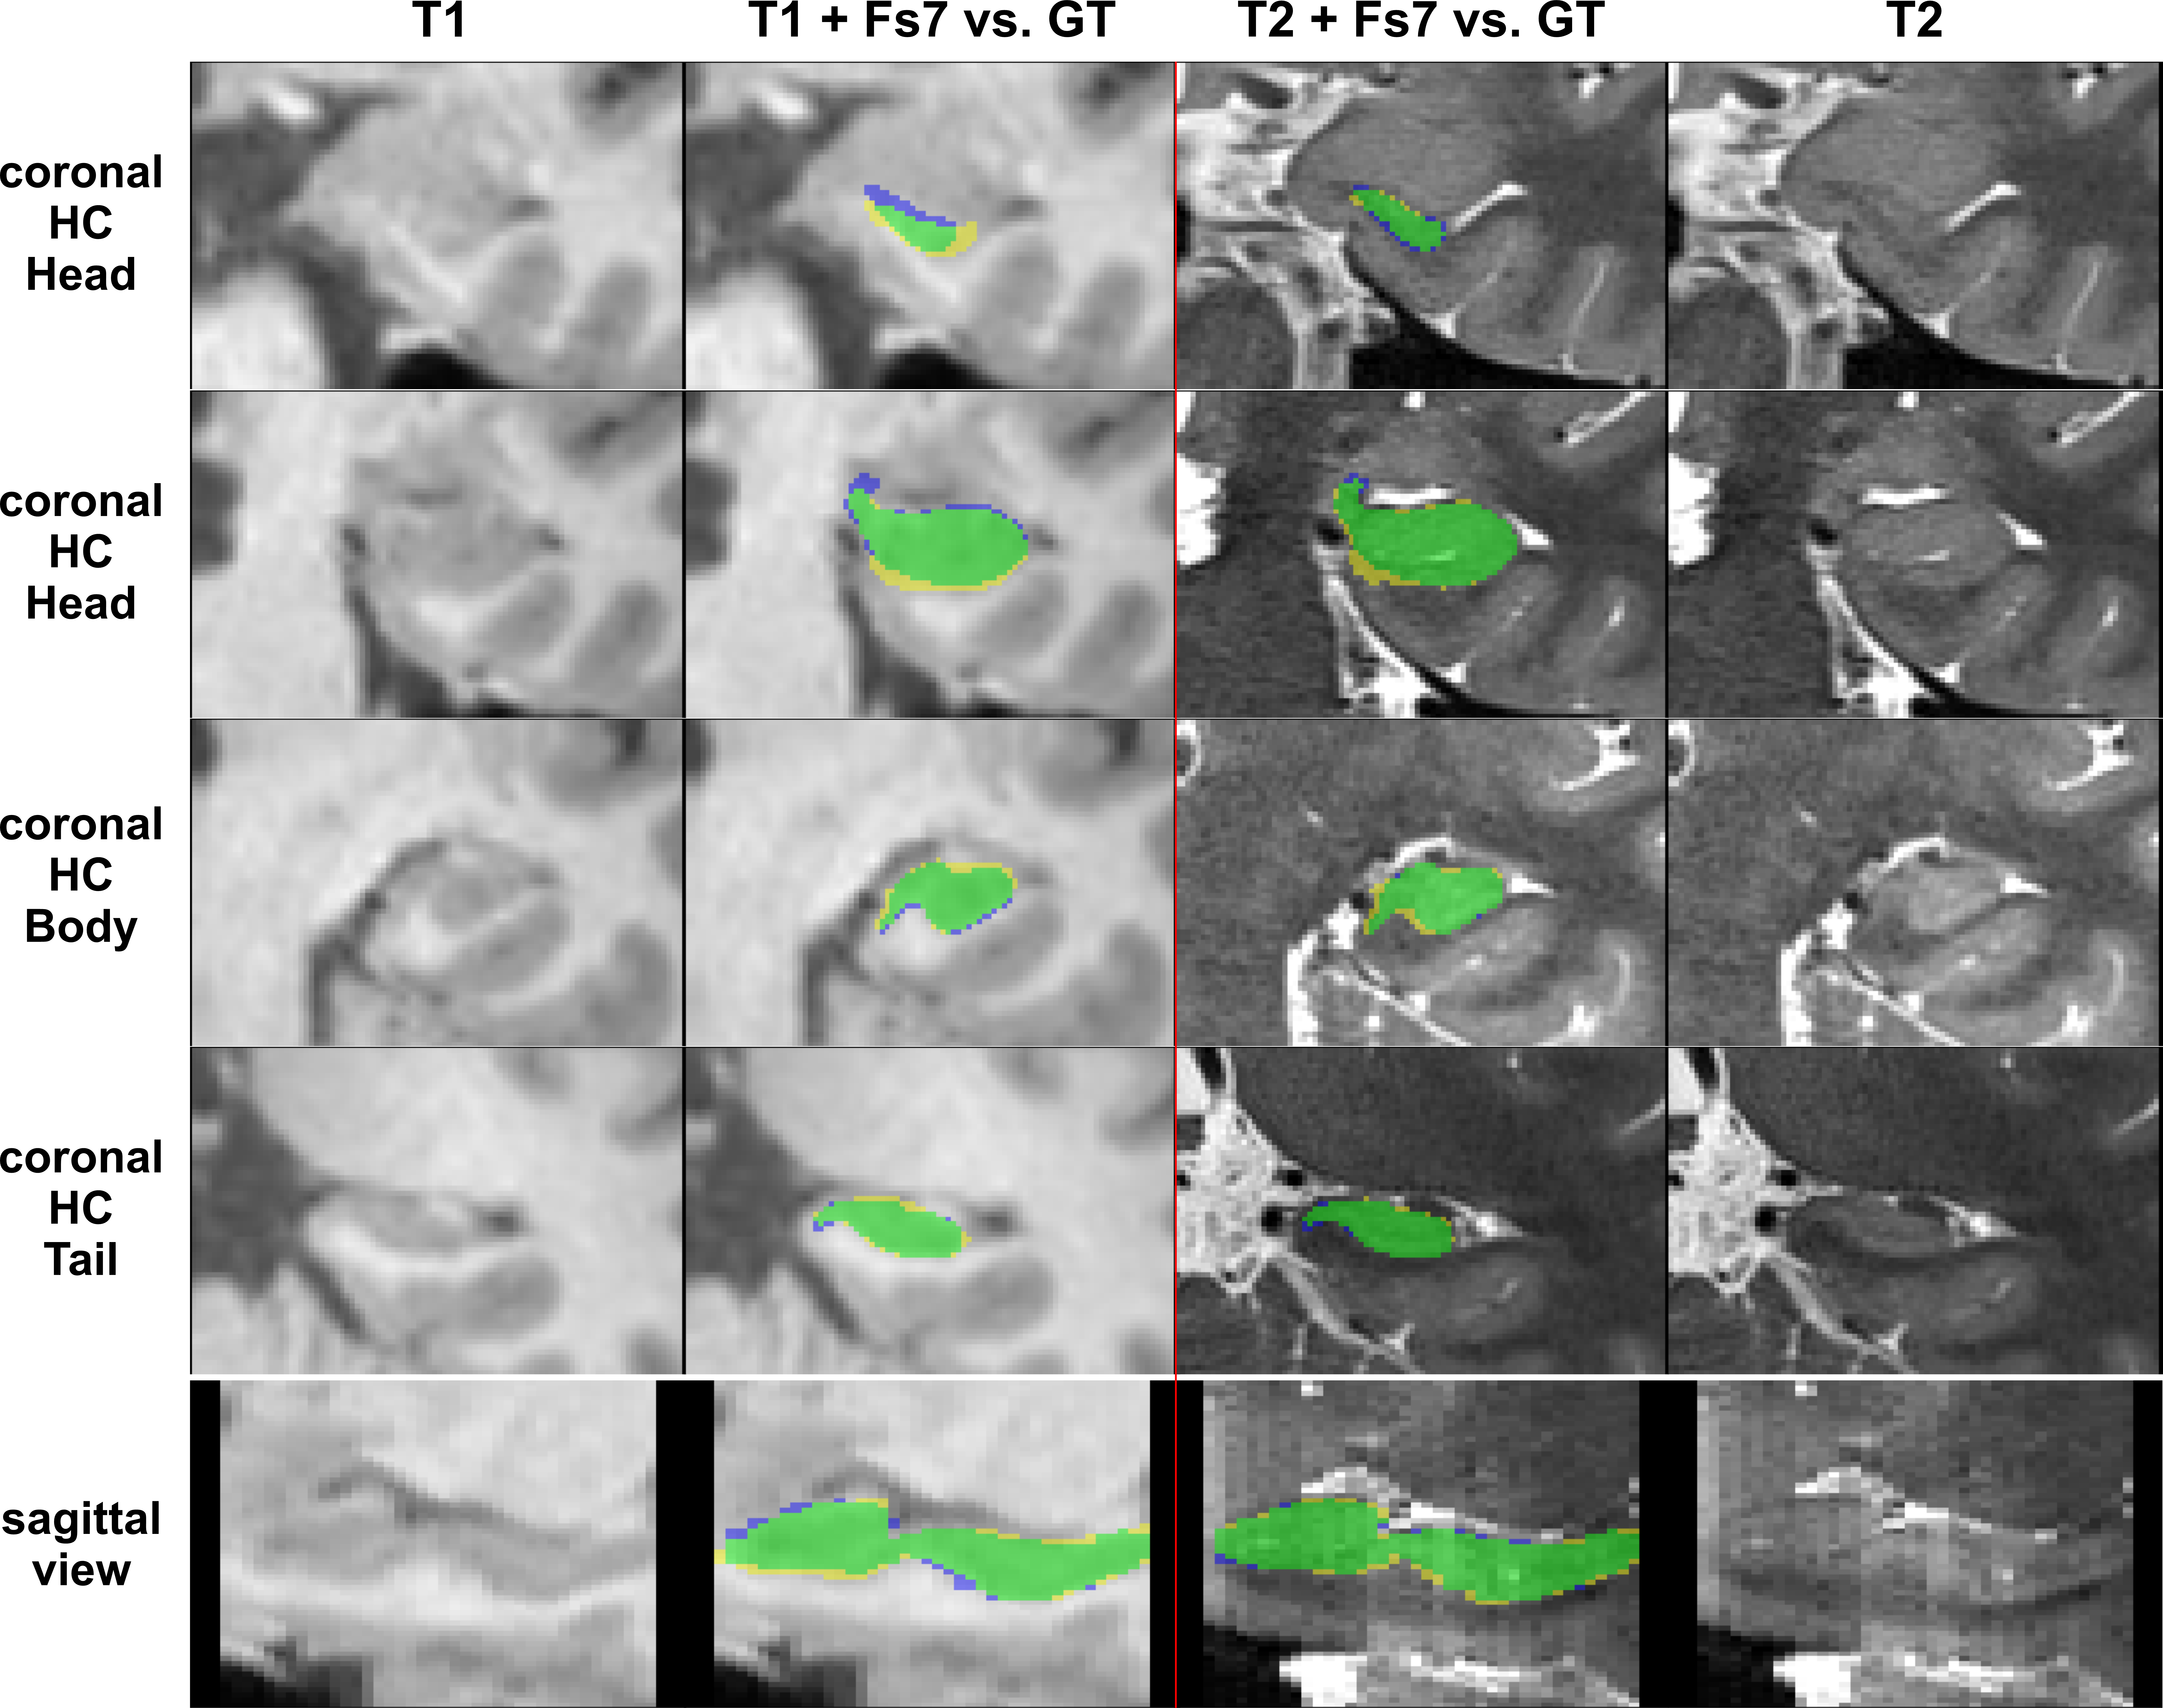

The performance of all segmentation approaches was compared via Dice similarity coefficients (DSC) against our manual GT, averaged over all cross-validation sets. HC segmentation from FreeSurfer v7.3.2 (Figure 4) achieved the lowest results, where using only T1 inputs yields 76.7±4.6% and using T1&T2 inputs results in 77.4±4.3%.

Figure 4: FreeSurfer segmentation. Columns left to right: 1. shows T1 patch; 2. shows comparison of the T1-based FS7-mask vs. the GT; 3. shows the T1+T2 based FS7-mask vs. the GT; 4. shows the registered T2 patch. Top four rows depict coronal slices of the HC-head, HC-body, and HC-tail. The last row shows a sagittal slice with the mask comparison. Legend: green = True Positives, yellow = False Positives, blue = False Negatives; FS7-mask/CNN-mask = yellow+green, manual GT = green+blue.